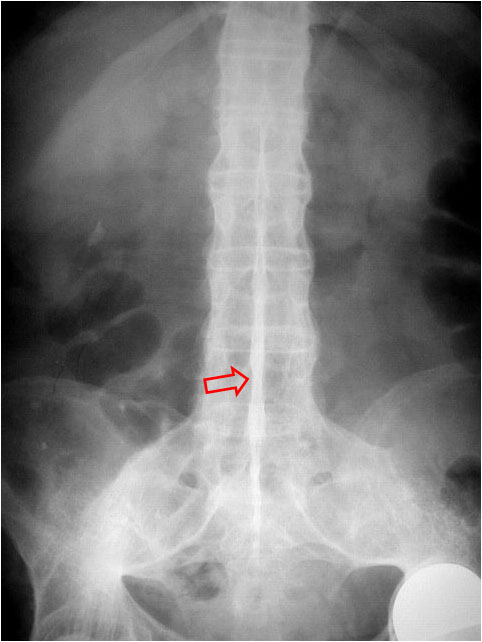

Otro ejemplo de este signo. Ambos riñones están excretando contraste ya que la columna en caña de bambú fue un hallazgo casual en la urografía de este paciente.

SIGNO DE LA DAGA

Signo de espondilitis anquilosante en la radiografía anteroposterior de columna lumbar. La daga es el nombre que recibe la línea radiodensa central (flecha) que corresponde a la osificación de los ligamentos supraespinosos e interespinosos.

En la imagen también vemos el signo de la columna en caña de bambú y la fusión de ambas articulaciones sacroilíacas, característicos de la espondilitis.